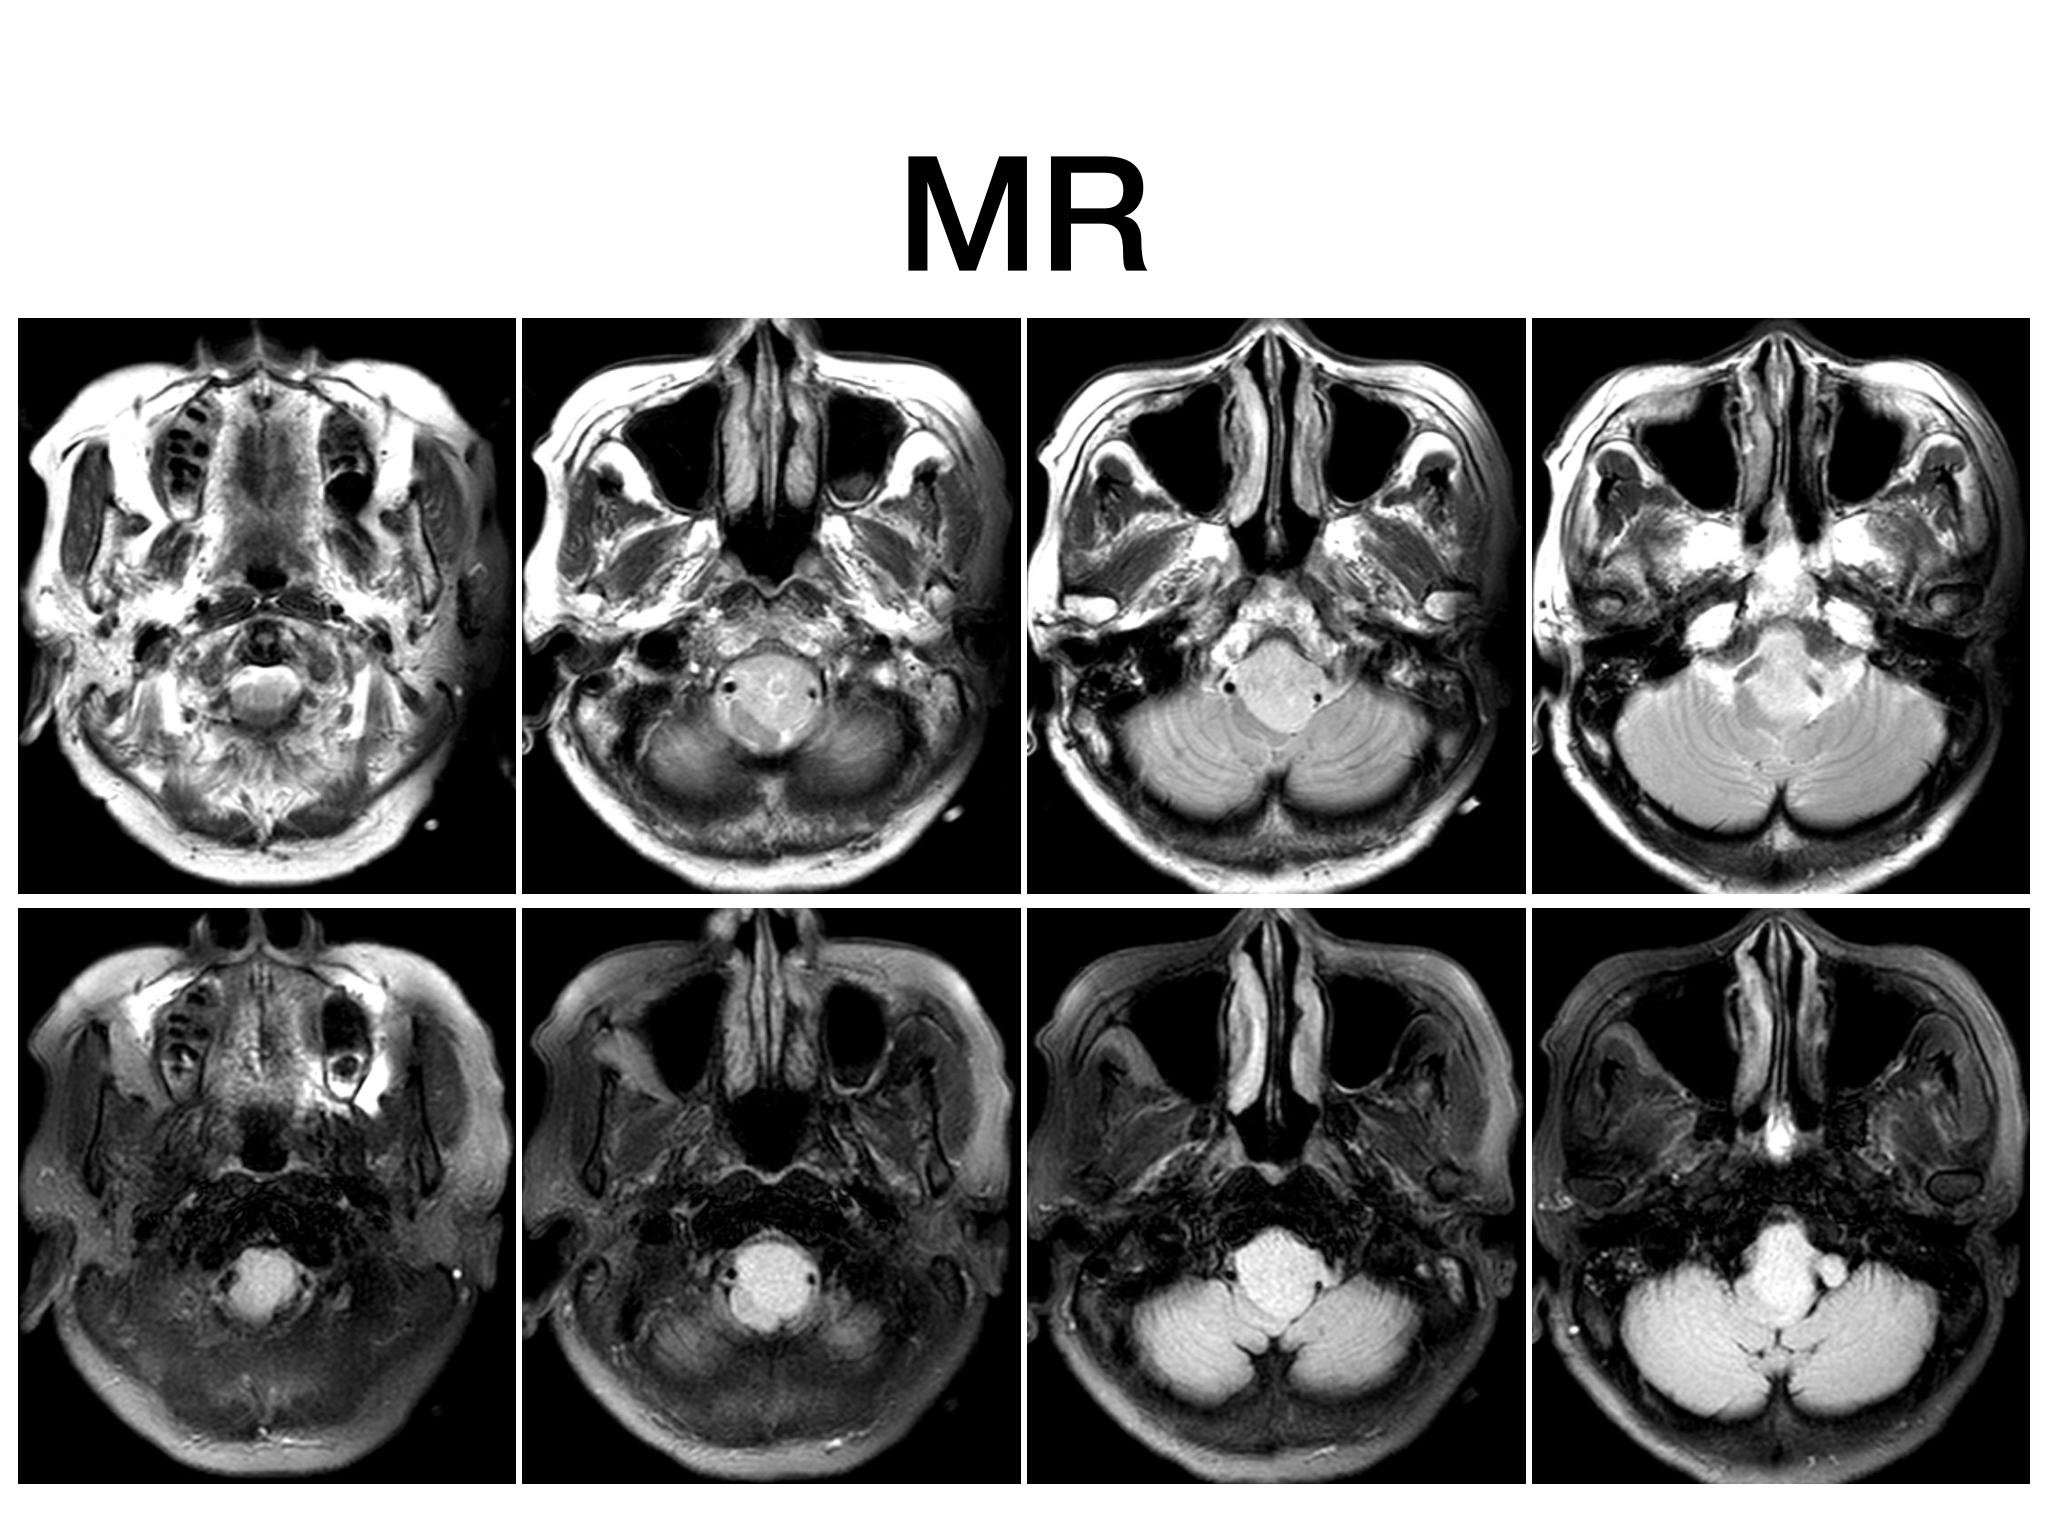

汇报一例后颅底肿瘤手术。为枕骨大孔巨大腹侧型脑膜瘤,该患者高龄,同时合并肺Ca,术前2周急性加重,枕骨大孔疝前期表现,术前已有延髓压迫及后组颅神经麻痹表现。经详细评估后采用远外侧经髁窝入路,最大化显露,重点保护延髓、后组颅神经,尽可能“零骚扰”。术中肿瘤质地韧,血供一般,与肿瘤上极与后组颅神经黏连紧密,最终99%切除,残留约1%,术后顺利康复出院,无新发症状,为后续进行肺部病变化疗创造有利条件。

远外侧经髁窝入路切除大型枕骨大孔腹侧脑膜瘤